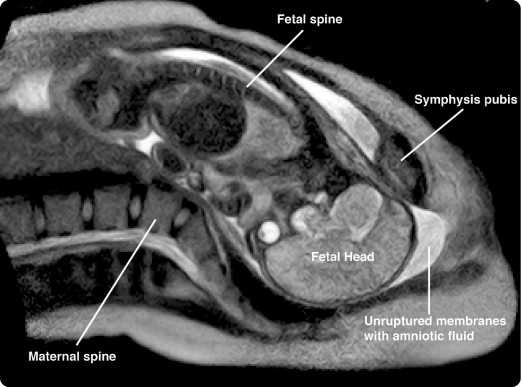

Είναι η πρώτη φορά που καταγράφεται βίντεο γέννας σε μηχάνημα MRI real-time. Στην ταινία υπάρχει πια υπό επιτάχυνση real-time MRI γέννα που ξεκινά με τη μητέρα να προσπαθεί να γεννήσει και τις αμιοτικές μεμβράνες στη θέση τους. Τελειώνει όταν το μικρό μας έχει… δείξει το κεφαλάκι του!